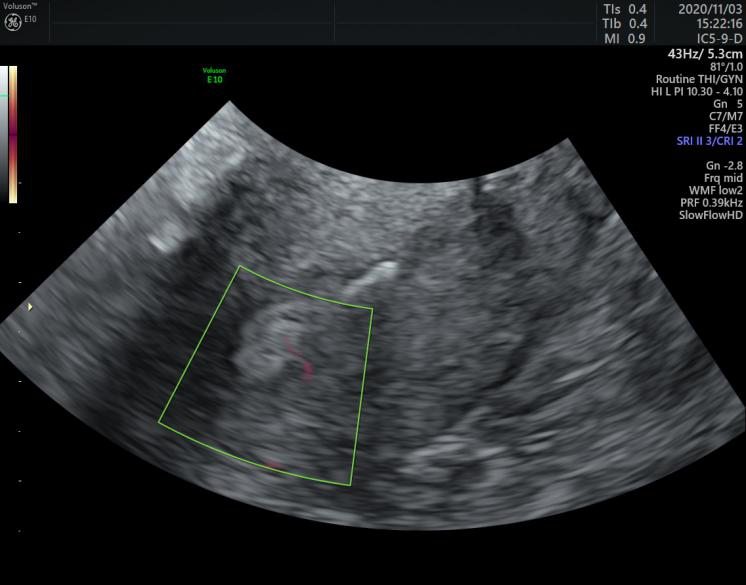

煊流成像技术:SlowflowHD:快速、直观显示微小血管

能否看清子宫内膜息肉的微小血管决定了诊断的准确性

胼胝体周动脉超低速血流灌注状态

Radiantflow:更少的频闪和增强的血管边界显示